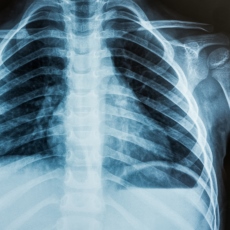

Los efectos biológicos dependientes de la dosis se vuelven medibles por encima de 50 mSv (milisieverts) y una dosis de cuerpo entero de más de 10 Sv (sieverts) es universalmente letal. La dosis de radiación promedio por persona en el Reino Unido es de 2, 6 mSv por año, de los cuales 2, 2 mSv son de fondo y 0, 4 mSv se relacionan con la exposición médica. Las investigaciones diagnósticas suelen implicar dosis entre 0,02 mSV (radiografía de tórax) y 10 mSv (TC de abdomen). ¡Esto significa que una radiografía de tórax equivale a 3 días de radiación de fondo y una TC de abdomen equivale a 4, 5 años!